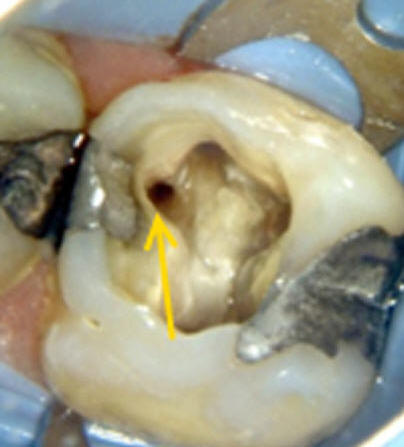

Cuarto conducto en molares superiores (Color amarillo conducto mesio-palatino)

La raíz mesiovestibular es achatada en sentido mesiodistal y amplia en sentido vestibulopalatino.El conducto mesiovestibular con frecuencia es curvo y de sección en forma de hendidura. La existencia de dos conductos en esta raíz, puede presentar la siguiente configuración:

• uno vestibular (Color azul)

• y el otro palatino (Color amarillo)

Estos conductos pueden unirse a distintos niveles, terminando en un foramen único o ser de trayectoria independiente hasta el ápice y terminar en forámenes separados. Son atrésicos y de difícil tratamiento en especial el palatino.